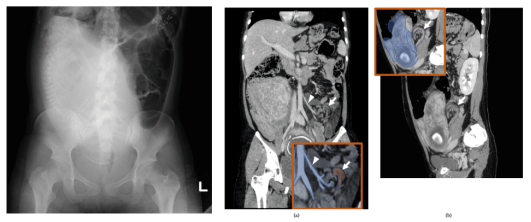

图2.(a)腹部对比增强计算机断层扫描(CT)(冠状位图)显示肠系膜下动脉(箭头)周围有乙状结肠扭转(箭头)。(b) 腹部增强CT(矢状视图)-扭转部分位于子宫背侧(箭头)

进行CT增强扫描以确定诊断和治疗方案。腹部增强CT扫描显示子宫背侧有扭转。横结肠近端明显扩张,远端塌陷。肠壁内没有对比剂摄取不良的区域(图2a-b),并且发现3小时前腹部平片未发现的腹水。CT参数如下:螺距55,120千伏,400-600毫安。估计胎儿辐射量为23.12 mGy。